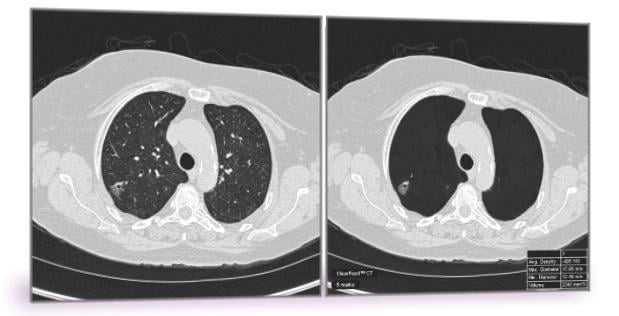

ClearRead CT is the only FDA-cleared device to support concurrent reading, allowing for faster reading with proven superior automatic nodule detection performance for all primary nodule types, including solid, sub-solid and ground glass nodules.

The software is comprised of two tools: ClearRead CT | Vessel Suppress and ClearRead CT | Detect. Deep learning enables the vessel suppression technology to assist both machine and humans in the detection and characterization of all primary nodule types, allowing for previously unattained nodule detection performance.